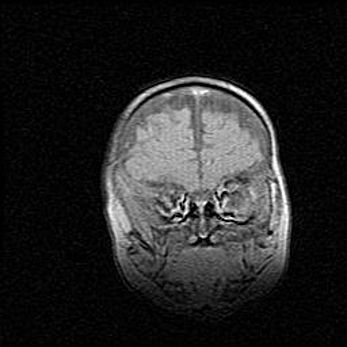

Открытая гидроцефалия.

Возраст: 9 месяцев 12 дней

Вес: 6800 г

Пол: мужской

Окружность головы: 41,5 см

Срок гестации: 28 недель

Гидроцефалия головного мозга у новорожденных имеет характерный признак: опережающий рост окружности головы приводит к визуально хорошо определяемой гидроцефальной форме сильно увеличенного в объёме черепа. Детские неврологи определяют следующие симптомы гидроцефалии у грудничков: выбухающий напряжённый родничок, частое запрокидывание головы, смещение глазных яблок к низу.